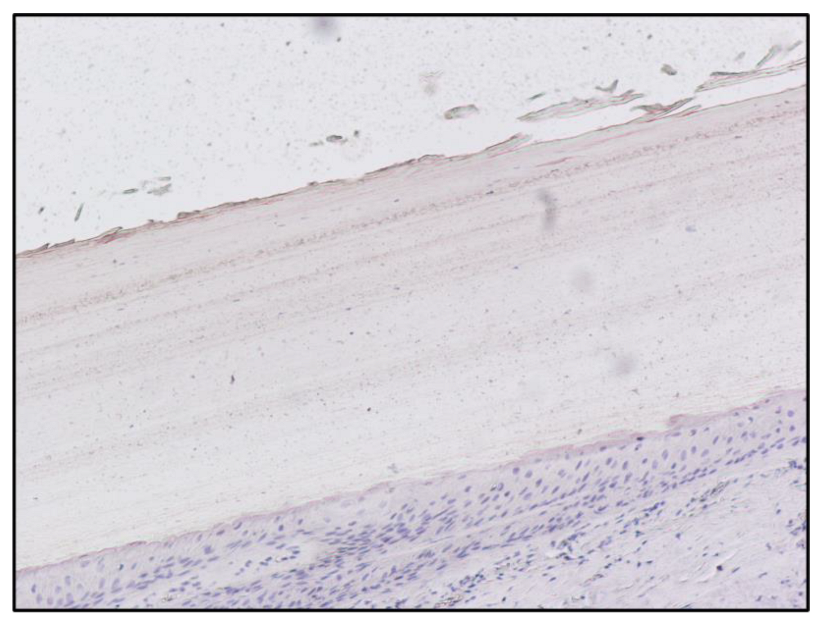

| Subject C (Figure 5) | 1,228,800 | 2.252 |

| Subject C matrix | Instrument | Morphine | 6-MAM | Codeine | Methadone | EDDP |

| Blood | GC-MS | Negative | Negative | Negative | Negative | Negative |

| Pubic hair | UHPLC | 2.2 ng/mg | 4.43 ng/mg | Positive | Positive | Positive |

| Fingernail | UHPLC | Negative | 1.03 ng/mg | Negative | Negative | Negative |